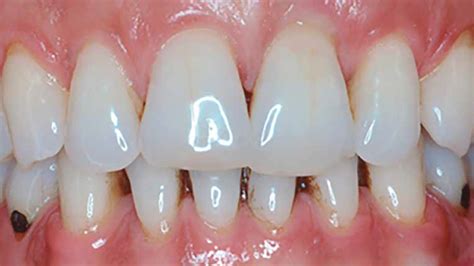

La sonda periodontal se utiliza para determinar la condición de los tejidos periodontales, incluyendo:

- Profundidad del sondaje y el nivel de inserción clínico o relativo.

- El estado del epitelio crevicular.

- La presencia de hemorragia al sondaje.

Es importante observar si existe o no sangrado al sondaje, ya que la presencia de inflamación periodontal es un indicador clave de enfermedad.

- Diagnóstico preciso de la enfermedad periodontal.

- Planificación del tratamiento periodontal.

- Monitoreo de la respuesta al tratamiento.